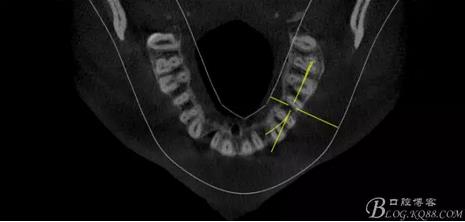

(1) 檢查:12唇側(cè)牙齦可見竇道,牙體顏色較鄰牙暗,無光澤,形態(tài)完整無缺損,唇側(cè)及近遠中向未提及牙周袋。腭側(cè)齦緣輕度紅腫,舌側(cè)窩可探及裂溝,可見浸墨狀痕跡,沿裂溝舌側(cè)探診牙周袋深大于11mm,除患牙外全口牙周狀況良好,為探及牙周袋,牙齦色粉紅。邊緣菲薄,質(zhì)地堅韌。12冷熱診無反應,叩診(+-),無明顯松動,無咬合創(chuàng)傷。12根尖x線片示,根管中三分之一中可見一斜向線樣透射影像根尖區(qū)及遠中根三分之一可見低密度透射暗影,錐形束CT示12根尖區(qū)唇腭向骨吸收已穿通,根面溝達根中三分之一卷曲分出另一牙根,再未見其他明顯的根管系統(tǒng)。